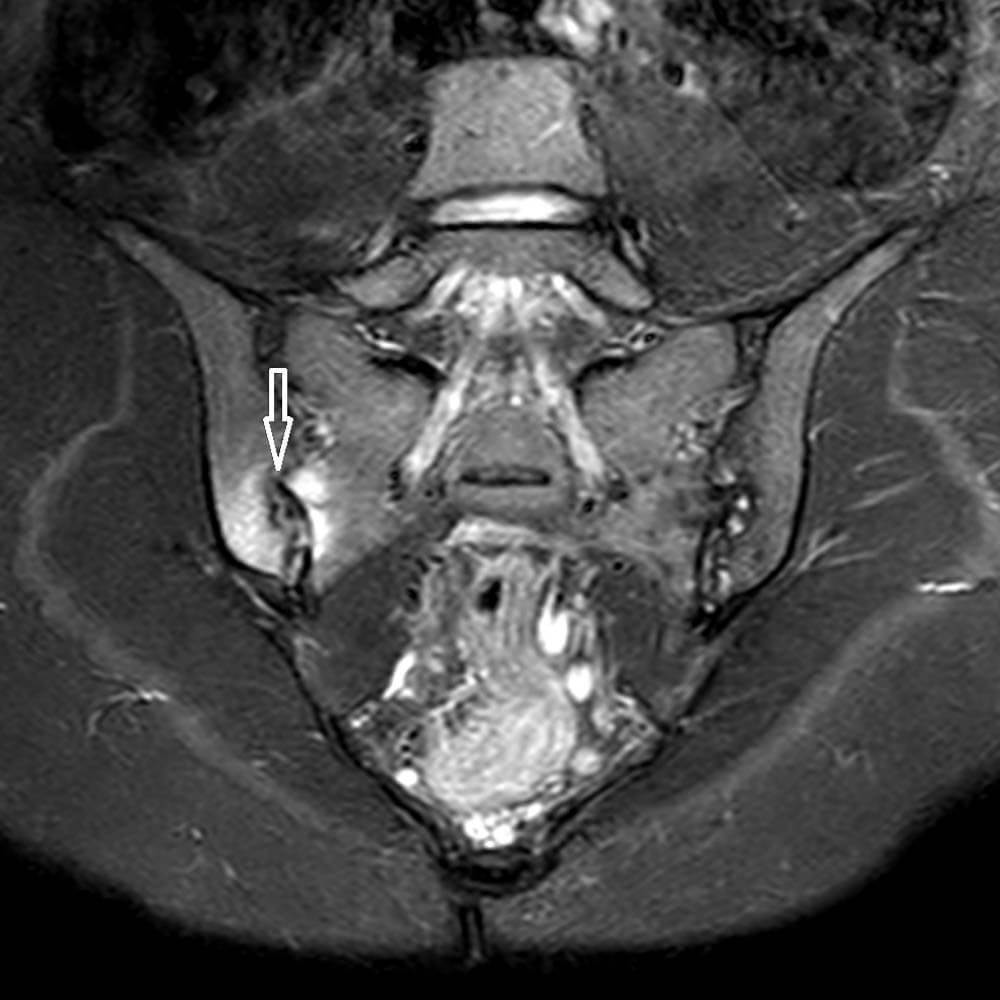

Entzündung

Entzündliche Erkrankung der Iliosakralgelenke.